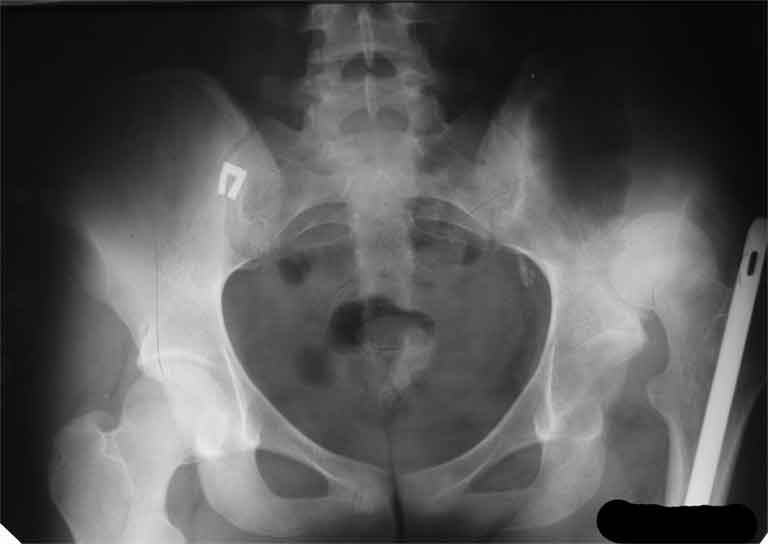

AV> опираясь на стул. На ногу не наступает. Укорочение 8 см. Иногда

А за счет чего такое укорочение? По снимку не видно соответствующего дефекта. Ну плюс приводящая контрактура - но все равно как-то уж больно много. Может, сделать снимки и таза обзорный с обоими проксимальными отделами бедра, и коенный суставов с приложенной линейкой какой?

Судя по снимку, максимум истинное укорочение около 4 см, что может быть коррегировано интраоперационно. Вопрос в другом: куда ставить ацетабулярный компонент в истинную или во вновь сформированную ( впадина диспластичная).

Невозможно не согласиться с Анатолием, чтобы заниматься адекватным планированием как минимум прямая проекция таза должна быть сделана, как

максимум для оценки состояния мышц( насколько реально возможно низвести бедро) прямая проекция таза с тракцией за больную ногу.

The X ray that you provided does not show 8 cm of shortening. Perhaps you could send one showing the whole pelvis and proximal femurs.

I agree with Dr Eid's comments. The origin of the 8 cm leg length difference is a puzzle. Is this a clinical measurement? In that case contracture of the joint might affect the measurement. Can we see an AP pelvis to include both hip joints (including a calibration object with a known length) so that the difference in leg lengths that can be ascribed to the hip deformity and bony reabsorption can be measured. This sort of xray will help with templating for the TJR also. I would be very tempted to do a one stage procedure and accept some shortening. Shoe lifts should take care of a 3-4 cm difference.

До травмы проблем с ногой не было. Укорочения, болей и т.п. не отмечал. Сегодня перемерял укорочение - меньше 7 см намерять не

получается :)

По уровню малых вертелов (с учетом рентгеновского увеличения) получается 5 см. Клинически ногу низвести путем тракции невозможно. Из движений - сгибание до 40*, остальные движения "символические".

Ортопедическое укорочение пострадавшей ноги может быть и 7, и 10 см. за счет контрактур в тазобедренном суставе, а вот истинное укорочение, судя по представленным рентгенограммам, вряд ли больше 4 см.